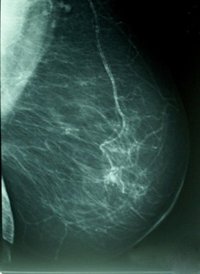

La Unitat de Consell i Cura Oncològica (UCCO) del Campus CIMA de Sanitas Hospitales ha publicado recientemente el libro 'Mitos y Realidades en Oncología', para clarificar mitos o creencias como que los anticonceptivos orales, los móviles y los sujetadores con aros causan cáncer de mama.